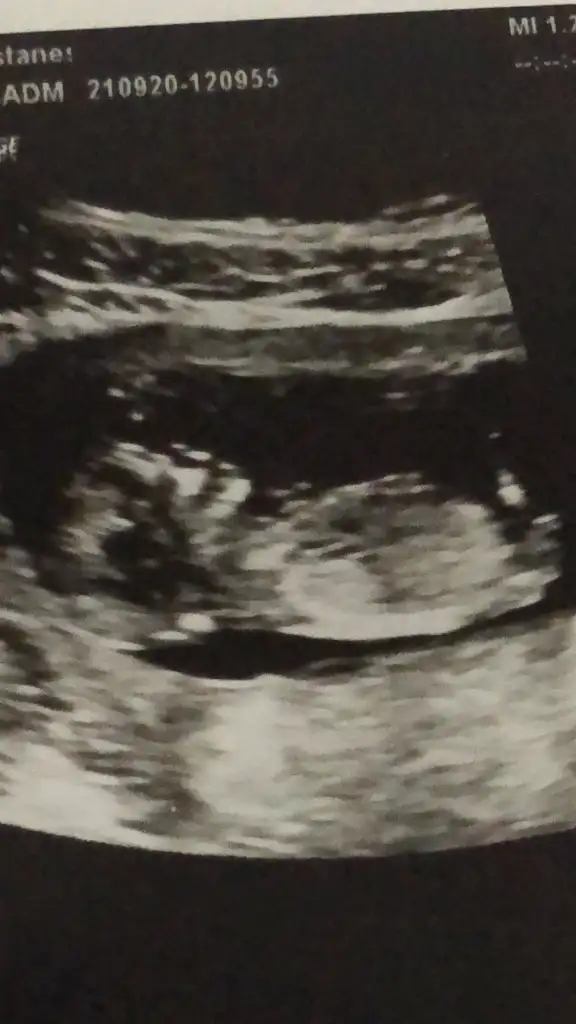

USG uzak cekermisin puslu gibi net değil odaklayin çekinMerhaba.12+2 burda cinsiyet tahmini yapabilir misnz

Şu görünen nub acısı %45 değil ama %40 yani çokta paralel görünmüyor onun için erkek gibi diyorumYaaa öyle mi diyosun nerden peki canm doktor acklama yapmadı cok mrak ettm

Şu görünen nub acısı %45 değil ama %40 yani çokta paralel görünmüyor onun için erkek gibi diyorum

Erkek gibiElimde bu fotolar var canm☺

Evet erken zamanlarda yanilma payi oluyor.Ama nub erkek gibi gozukuyor.Insallah gonlunuzdeki olurÖyle mi diyosunuz doktorum cok erken bilgi icin dedi

Ne kadar net bencede erkekŞu görünen nub acısı %45 değil ama %40 yani çokta paralel görünmüyor onun için erkek gibi diyorum